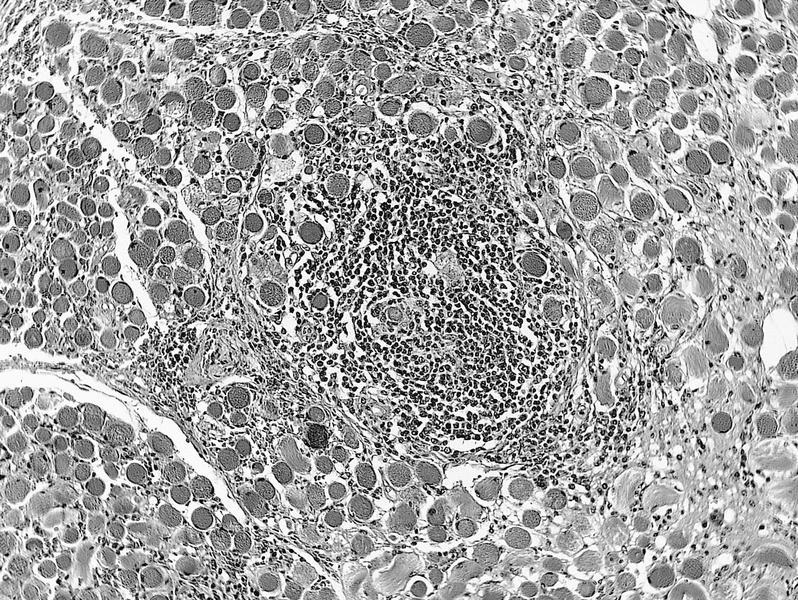

Microscopic (histologic) description

Microscopic (histologic) images

AFIP images

Microscopic (histologic) description

- Rosai-Dorfman related:

- Large histiocytes, some with lymphocytophagocytosis, lymphocytes and plasma cells, often with prominent fibrosis

Microscopic (histologic) images

AFIP images

Idiopathic sclerosing inflammation

Definition / general

Microscopic (histologic) description

Microscopic (histologic) description

- Desmoplasia, sparse lymphocytes (usually T cells), histiocytes, plasma cells, neutrophils, eosinophils